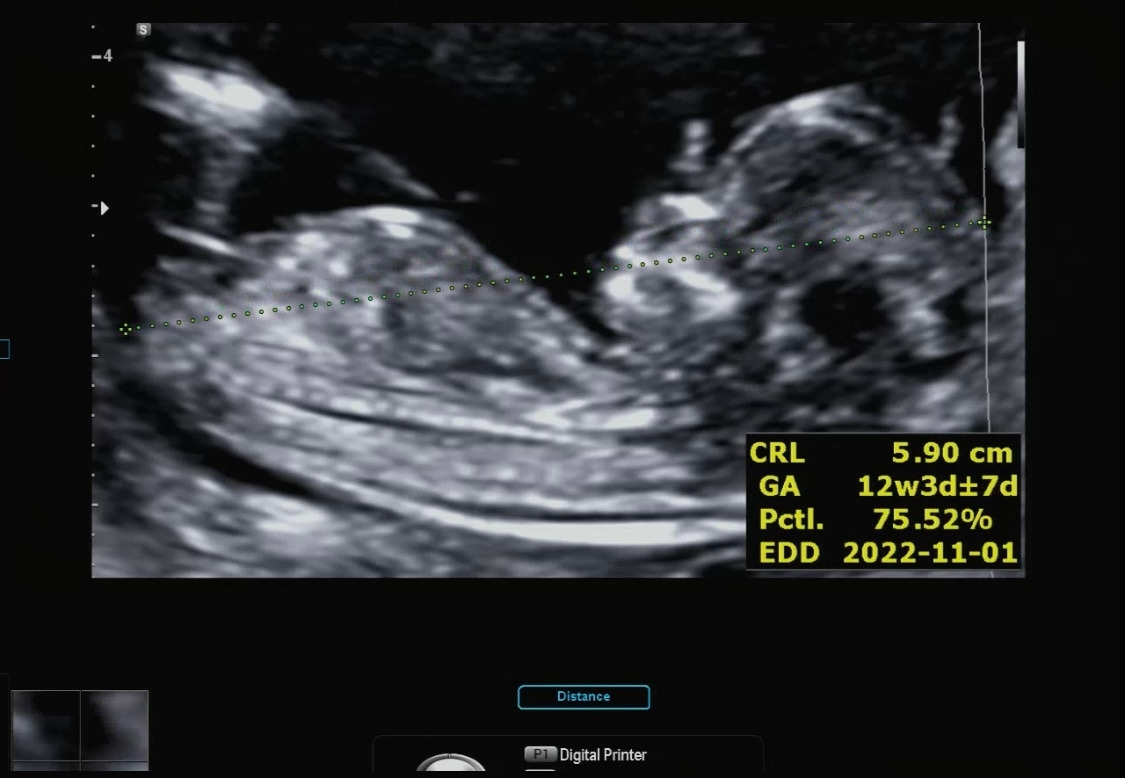

12주.jpg

그나마 가랑이 사이를 보여 준 영상을 캡처 한 부분이다. 잘 안 보이는데 밋밋해 보여서 여아 같지만 뭔가 또 보이는 것 같기도 하고....ㅎㅎ 다올이는 남자일까 여자일까?

12주 각도 법에 의하면 옆으로 누워있는 사진을 봤을 때 남아는 약간 위쪽 각도로 생식기가 보이고 여아는 수평하게 일자로 생식기가 보인다고 하더라 (ㅎㅎㅎ) 정확한 건 아니다. 성별이 궁금한 엄빠들의 부단한 노력의 결과..

각도 법을 봐도 뭔가 딸아이 같다. 근데 태몽은 남아였는데...(?!) 남자 아이던 여자 아이던 나는 둘 다 좋지만 그냥 궁금하다. 성별이 ㅎㅎ 그리고 남아면 힘들다고 주변에서 하도 그래서 체력을 키우고 마음의 준비를 해야 할 것 같다.